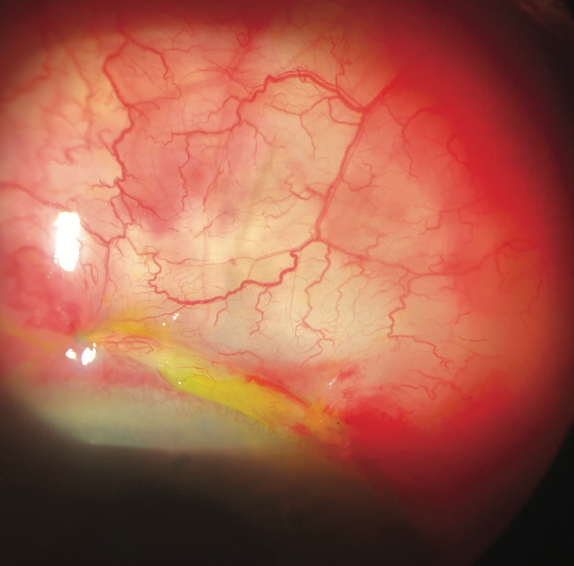

Yoshihiro Yonekawa, MD, reports on the findings of an investigation looking at the prevalence of endophthalmitis following minimally invasive glaucoma surgery.